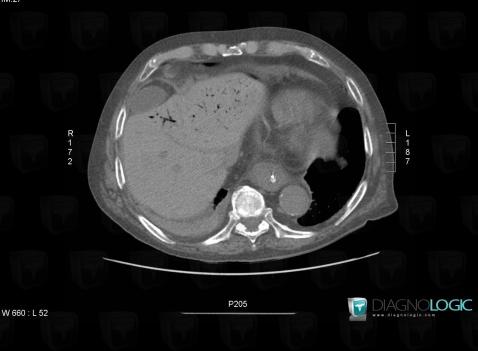

Aéroportie, Foie, Veine porte et ses branches, Scanner

Voici les informations spécifiques à l'image clé ci dessus:

- Diagnostic Aéroportie, Localisation(s) Veine porte et ses branches, comportant les gammes Foie, comportant les gammes